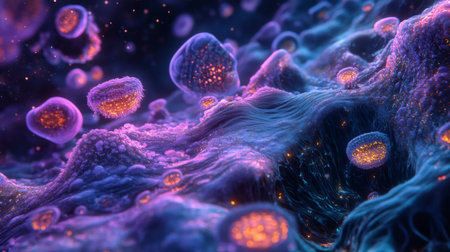

Colorful glowing microorganisms are visible under the microscope, showing their intricate structures.